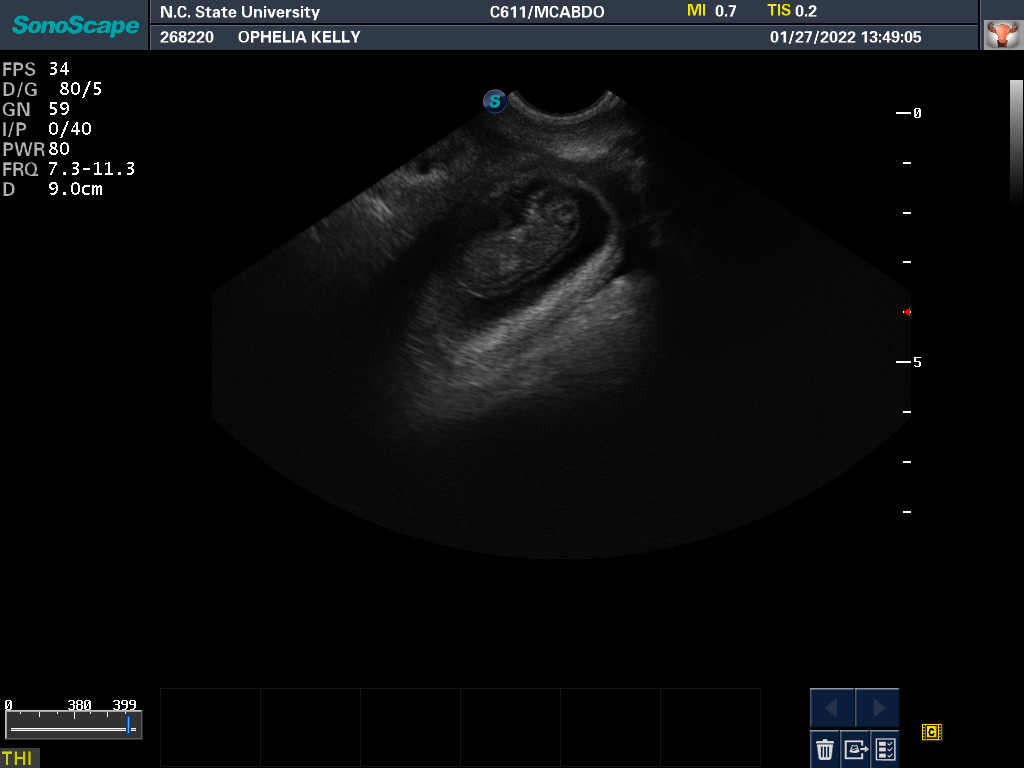

Ultrasound today by the theriogenology (reproduction) veterinarians at NC State University showed that Ophelia is pregnant with three puppies, possibly four puppies. (It can be difficult to accurately count puppies using ultrasound.)